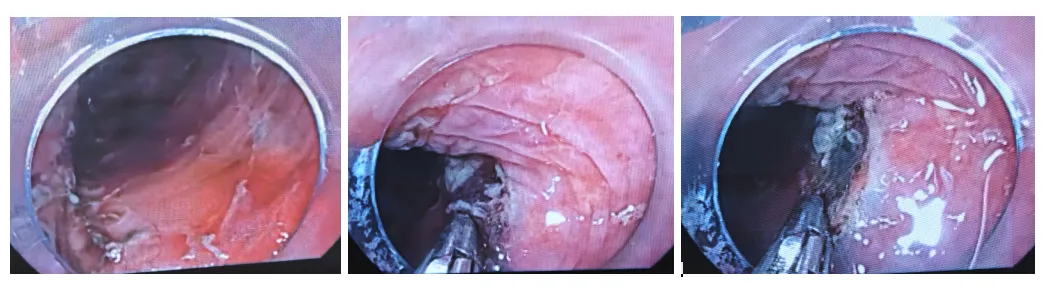

11:06边补水边剥离11:08病灶切下来了。

11:09创面处理,对创面可疑的出血处给予电凝止血

手术结束一般术后一周复查胃镜如果术后病理浸润到了粘膜下层,建议外科手术,不同意外科手术的患者也要建议放化疗